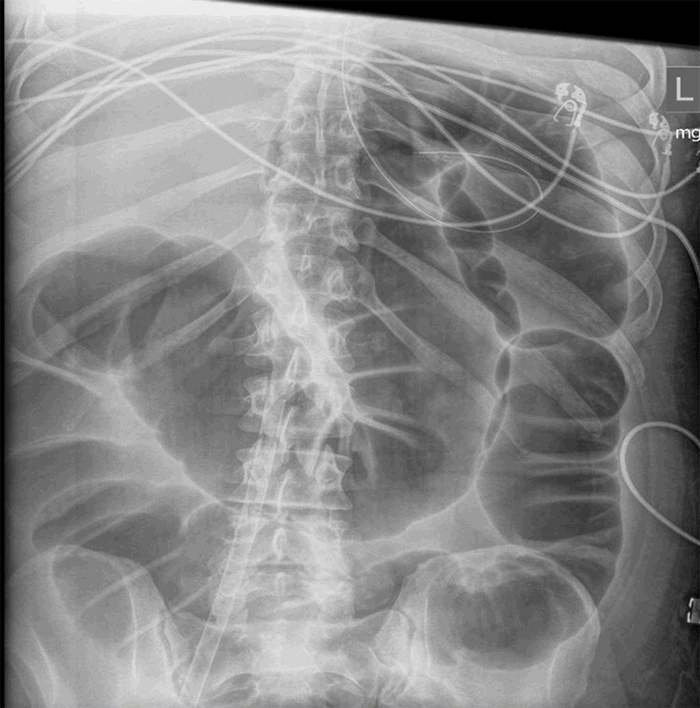

On laboratory examination, his white blood cell count (WBC) was 6900/uL, with lymphopenia of 19.3 percent (normal: 22 to 44 percent). D-dimer was initially normal at 458 ng/mL (normal: <500 ng/mL) but continued to rise, with a peak at 3750 ng/mL. Serum fibrinogen level was elevated to 1034 mg/dL (normal: 150–400 mg/dL). Tests for respiratory syncytial virus and influenza were negative. Chest X ray showed bilateral linear lung atelectasis and scarring. CT angiogram of the chest showed signs of emphysema and chronic bronchitis (Figure 1a). A nasopharyngeal swab was sent for polymerase chain reaction (PCR) testing and was positive for COVID-19.

Figure 1. Case 1 CT imaging (a) CT angiogram of the chest showed signs of emphysema and chronic bronchitis; (b) CXR consistent with acute respiratory distress syndrome; (c) abdominal X-ray showing generalized large bowel dilatation

The patient was admitted for resuscitation and monitoring. He was started on hydroxychloroquine and azithromycin. His hospital course was complicated by coronary vasospasm that led to a new onset chest pain, ST segment elevation on electrocardiogram, bradycardia, and hypotension, followed by progressive hypoxemic respiratory failure and ARDS requiring admission to the ICU and intubation on the seventh hospital day (Figure 1b) as well as shock requiring vasopressors. He improved clinically in the ICU, and his ST elevation resolved, so he did not undergo percutaneous coronary intervention or received antiplatelet therapy. He was, however, started on heparin for deep venous thrombosis prophylaxis. Despite an initial ileus, he started having bowel movements and tolerated full nasogastric nutrition. Two weeks after admission, he started having a new and significant abdominal distension. An abdominal X ray was obtained showing severe gaseous distension of the colon measuring 12 cm at the cecum level, with gas noted within the rectum and no obstructive pattern (Figure 1c). The WBC was normal at 11,400 /uL. A rectal tube was placed, and the patient immediately passed a large amount of flatus and 600–1000 mL liquid brown stool; his abdominal distention improved. The subsequent clinical course of this patient has been published previously in the Annals of Surgery.3 Briefly, twenty-four hours after his last abdominal X ray, he developed a new leukocytosis to 22,000/uL, his abdominal distention worsened again, and a repeat abdominal X ray showed worsening colonic gaseous distension up to 13.5 cm at the cecum, now with signs of bowel wall pneumatosis. The patient was taken urgently to the operating room for an exploratory laparotomy. Intraoperatively, there was diffuse dilatation of the entire colon with patchy necrosis of the cecum, necessitating a total abdominal colectomy and an end ileostomy. His colon pathology showed ischemic large bowel with focal transmural necrosis.3 He was transferred to the ICU in critical condition. He subsequently developed acute kidney injury and was started on continuous veno-venous hemodialysis. Due to multiple end-organ dysfunction and poor prognosis, the family elected to transition him to comfort measures only as consistent with his previously expressed wishes. He subsequently died.